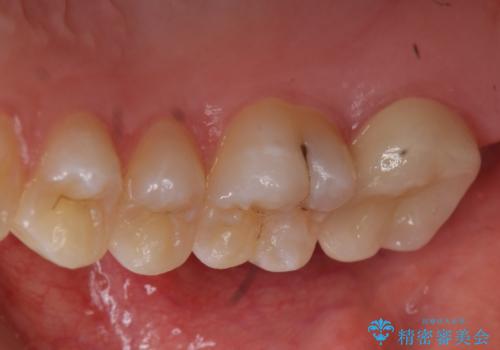

奥歯の虫歯 特殊な形をした歯の治療

頬側に咬頭が一つ多い歯であったのと、歯肉に近い位置が虫歯になっていたため、被せものでしっかり覆う治療を行いました。